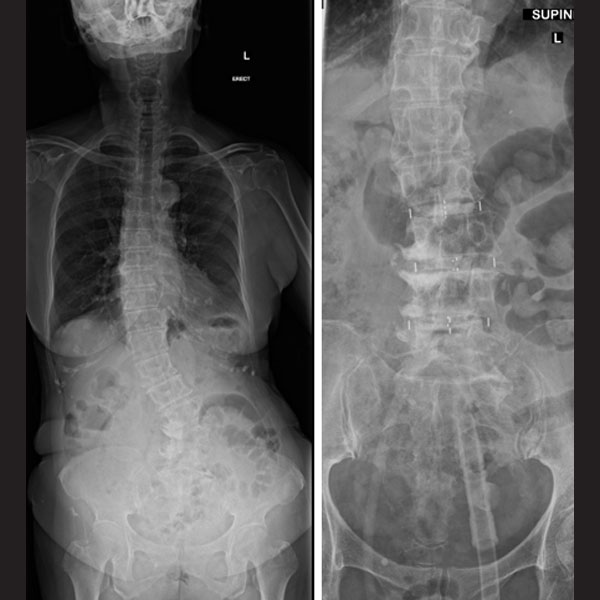

Note the coronal imbalance in the patient. Fusion performed using the pre-psoas approach, showing the vertebral bodies almost horizontal with a good correction of the coronal Cobb’s angle.